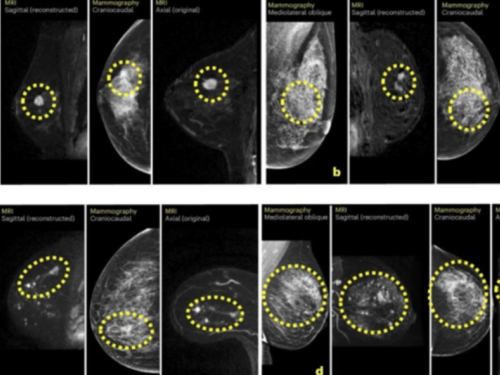

To bi kliničarima moglo omogućiti da pacijenticama s najvećim rizikom ponude i dodatna snimanja, poput magnetske rezonancije ili mamografije s kontrastom.